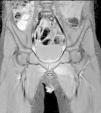

En la exploración de caderas presentaba dolor a la palpación en regiones inguinales y músculos aductores con limitación a la separación pasiva. No había limitación a las rotaciones de cadera y no se observaba hematoma, deformidad o tumefacción. En la analítica presentaba leucocitos 13.850/μl (N 11.770/μl, L 1.520/μl) con hemoglobina y recuento de plaquetas normales. La velocidad de sedimentación globular era de 50mm/h, la proteína C reactiva de 8mg/dl y la procalcitonina de 0,43ng/ml. La CPK era de 28U/l, siendo los parámetros de función hepática y renal normales. No se encontraron alteraciones en la radiografía de caderas. En la ecografía de caderas se apreciaba un discreto aumento del espesor de la cápsula anterior de ambas articulaciones con mínima cantidad de líquido intraarticular en el lado izquierdo (2,7mm de espesor). La resonancia magnética de caderas objetivó un engrosamiento y una alteración de la señal hiperintensa en secuencias T2 de la región de los aductores de forma bilateral con predominio izquierdo; en el músculo aductor largo izquierdo se apreciaba una imagen ovalada central, hipointensa en T1 e hiperintensa en T2, sugerente de colección (figs. 1 y 2). No se encontraron alteraciones en las articulaciones coxofemorales. Los hallazgos son compatibles con inflamación localizada en el músculo por piomiositis.